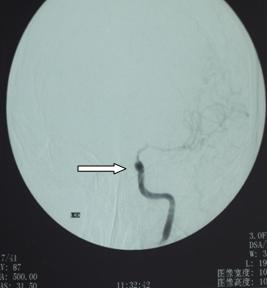

郭某,男,44岁,因口角左歪、言语不清3个月入院治疗。之前在东莞市某医院检查头颅MRA,提示左侧颈内动脉狭窄、闭塞,左侧大脑中动脉远段狭窄、部分闭塞(图一)。

治疗前MRA(图一) 治疗前DSA(图二)